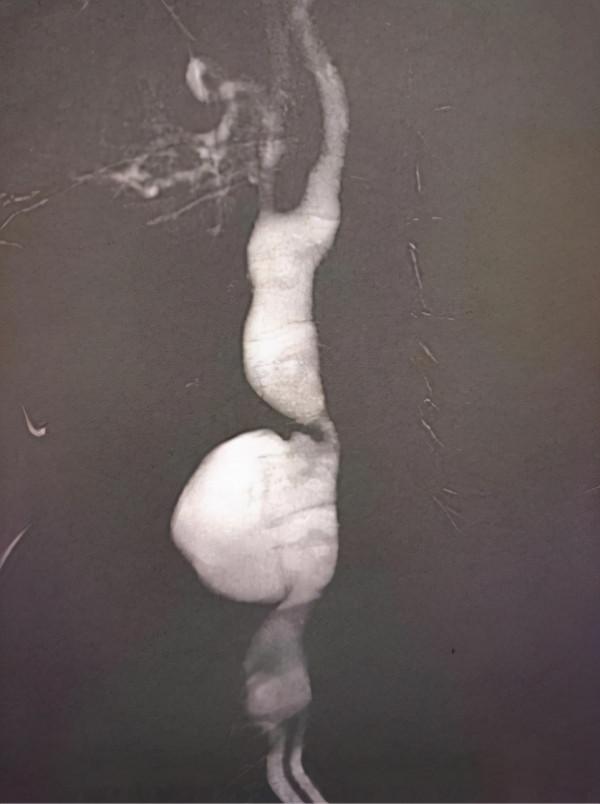

劉建林主任評估患者病情及檢查結果後,考慮頸動脈假性動脈瘤修復手術需全麻插管。術中造影顯示,左側頸總動脈中段血管破裂,區域性假性動脈瘤形成,瘤體較前明顯增大,破裂風險增加,在王吉昌主治醫師、劉嘉欣住院醫師協助下為該患者實施了介入微創手術,經準確測量及造影定位,放置一枚支架於破口位置,即在大腿根部行血管穿刺,將帶覆膜的支架植入到頸動脈破口處,從而阻隔頸動脈的破口,通俗的說是給血管加了個不滲血的“內襯”。手術過程順利,患者左頸部包塊搏動消失,目前病情穩定。術後超聲檢查提示瘤體內血流訊號顯示,提示破口被完全封閉。

術中造影結果,提示左側頸總動脈中段血管破裂,區域性假性動脈瘤形成